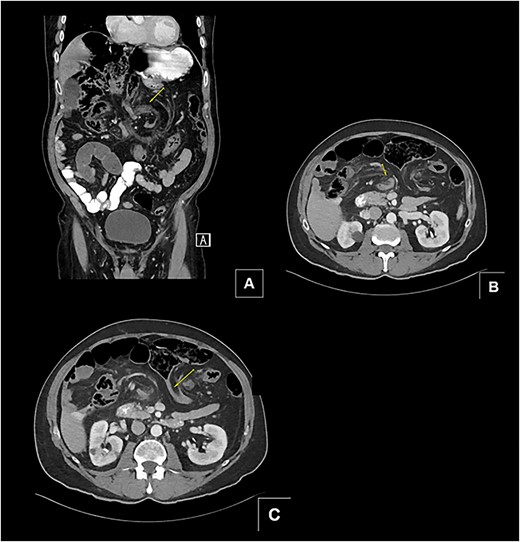

A 68-year-old male with a history of hypertension and no past surgical intervention presented with 2 days of diffuse abdominal pain, anorexia, and nausea. On admission, his vitals included a temperature of 98.2°F, BP of 149/79, pulse of 64, and SpO2 of 97% with a mildly distended abdomen with tenderness in the umbilical and epigastric regions. The labs were unremarkable. CTA/P showed two separate areas of mesenteric swirling: one contiguous to the distal small bowel, resulting in small bowel obstruction, and another at the distal transverse colon (Fig. 1A–C). The cecum was noted to be in the right upper quadrant. The patient was emergently taken to the OR and underwent a diagnostic laparoscopy. A cecal bascule was noted in addition to an internal hernia caused by a thick adhesive necrotic band arising from the colonic mesentery and omentum (Fig. 2). The bowel was viable, and the band was resected. The transverse colon was tortuous, but no hernia was seen. The cecum was brought down to the right lower quadrant, and a cecopexy to the abdominal wall was performed. The patient had an unremarkable postoperative course and was discharged on postoperativhernia was seen. The cecum was brought down to the right lower quadrant, and a cecopexy to the abdominal wall was performed. The patient had an unremarkable postoperative course and was discharged on postoperative Day 2.

(A and B) Two separate CT images showing mesenteric swirling in distal small bowel and colon. (C) CT image showing severe luminal narrowing of distal transverse colon.